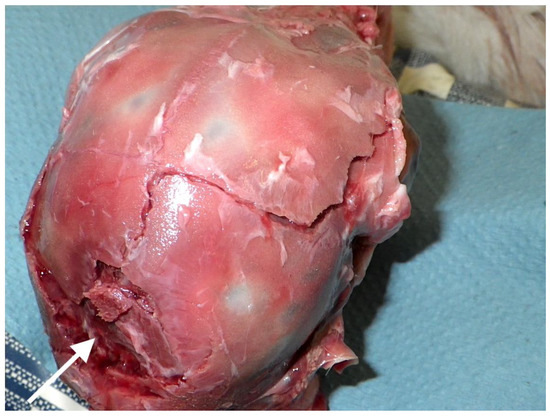

4.4. Fracture Pattern

4.5. Agonal Breathing